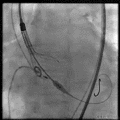

根部造影

定位胶囊腔

释放瓣膜

瓣膜释放至2/3时造影